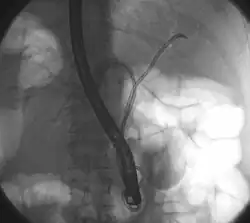

![]() опухоль Клатскина во время РХПГ. В левом и правом желчных путях. В обе половины вводили трубку с контрастом. в области слияния хорошо виден недостаток контраста. | |

Опухоль Клатскина, или внутрипротоковая холангиокарцинома – это холангиокарцинома (рак гепатобилиарной системы) в виде небольшого по размеру новообразования в месте слияния правого и левого желчных протоков и характеризующееся инфильтративным ростом по ходу желчного протока и через его стенку. Названа по фамилии врача Джеральда Клатскина, американского врача, работающего в Йеле.[1]